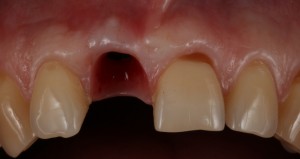

Не усложняйте! Немедленная имплантация или аугментация лунки?

По сути, для немедленной имплантации нет ограничений, за исключением случаев, когда имплантация не вписывается в общий план стоматологической реабилитации и ситуаций, когда невозможно хоть как-то стабилизировать имплантат в лунке зуба после удаления.